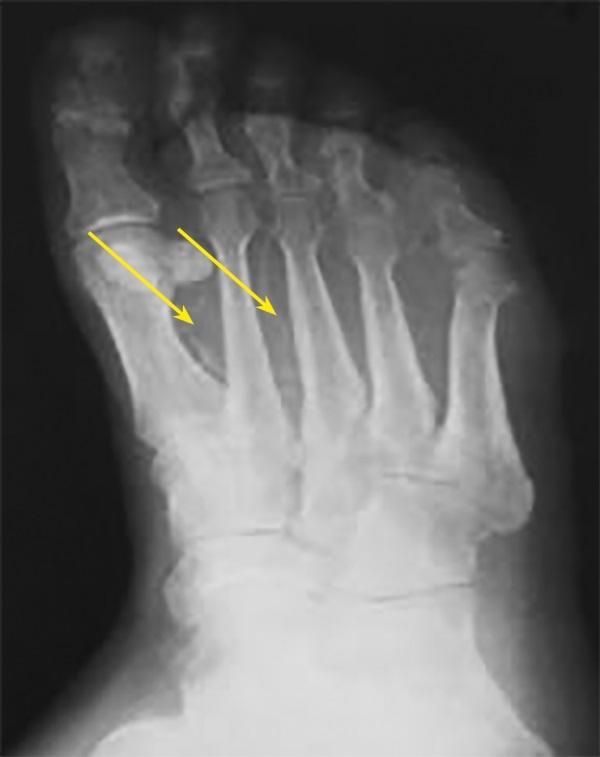

Abstract Image